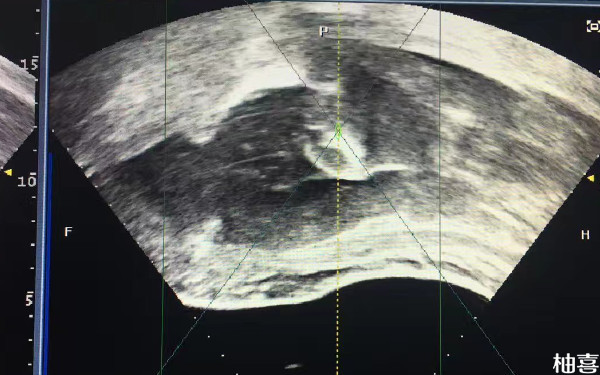

39周B超看男女还会翻盘吗?

39周B超看男女还是有可能会翻盘的,毕竟宝宝可能会存在遮挡的情况,导致判断不是很准确,只是有一点要注意,目前国内禁止非医学进行性别筛查和判断的,因此孕妇在医院产检时,医生并不会告知宝宝的具体情况,而网上的判断方法,并不能达到百分之百的准确率,因此还是有一定翻盘几率的。